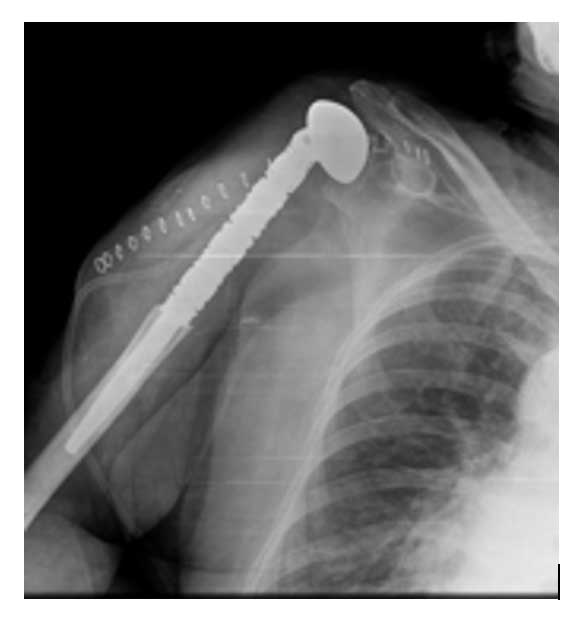

Ameliyat Sonrası: Sağ humerus üst uca uygulanmış çimentolu proksimal humerus tümör protezi görülmekte.